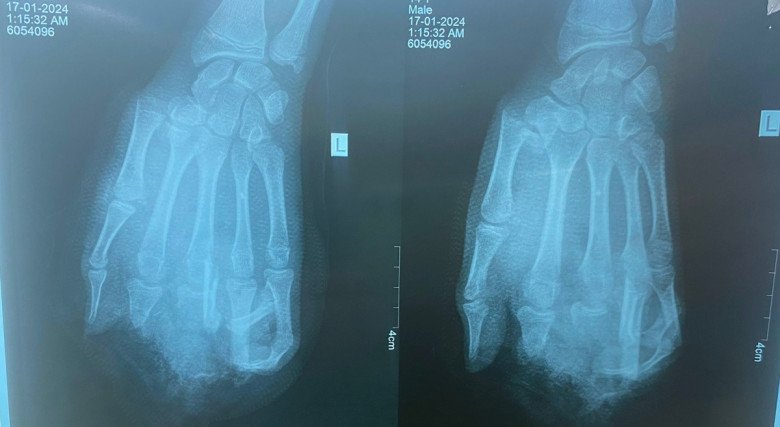

Hình ảnh phim chụp bàn tay nam thiếu niên bị nát do nổ bình gas khi ăn lẩu. Ảnh: BVCC.

Bệnh nhân là cậu bé 15 tuổi, đến từ Hải Dương và được chuyển lên một bệnh viện ở Hà Nội cấp cứu. Do tình trạng nặng nên bệnh nhân được chuyển tiếp tới BV Xanh Pôn để xử lý các tổn thương. Hiện các tổn thương đã được xử lý nhưng chức năng bàn tay của bệnh nhân sẽ bị giảm rất nhiều, ảnh hưởng lớn đến học tập, sinh hoạt và lao động sau này. Ngoài ra, do tuổi còn nhỏ nên người bệnh có thể bị ảnh hưởng tâm lý sau khi sự việc xảy ra.